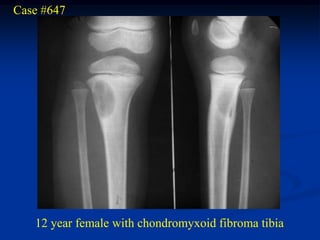

Case #647

12 year female with chondromyxoid fibroma tibia